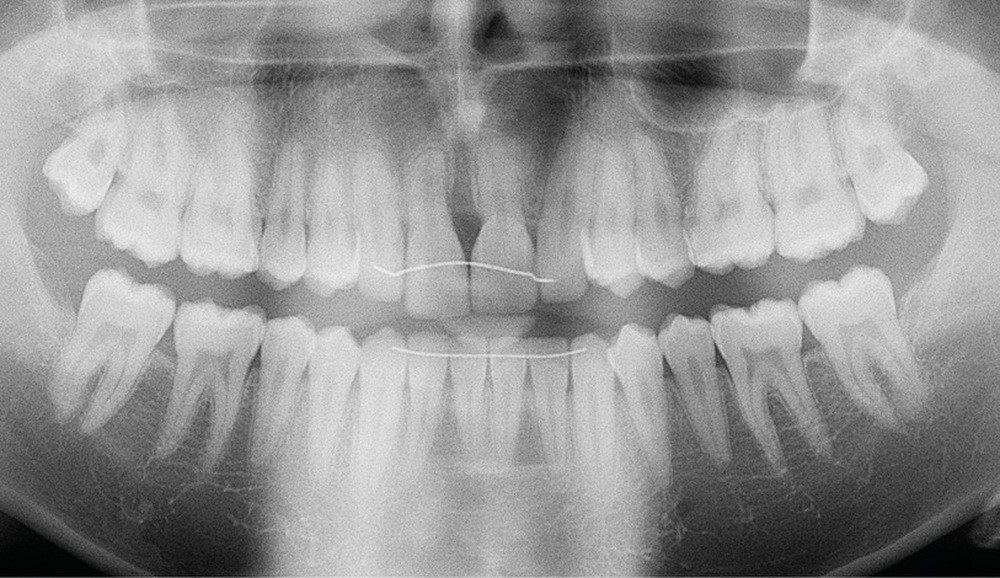

Antony, 11 ans se présente initialement pour une demande esthétique concernant ses deux incisives centrales qu’il trouve trop grosses (fig. 1a-c).

Le profil est convexe et associé à une inocclusion labiale au repos. Il s’agit d’une classe II squelettique sur un schéma facial normodivergent. Les rapports occlusaux sont de classe II bilatérale (complète au niveau molaire) avec des incisives inférieures vestibulo-versées. La 21 est géminée et la 11 vraisemblablement fusionnée avec un germe surnuméraire, sans altération de la formule dentaire. Du fait du diamètre mésiodistal fortement augmenté des incisives centrales, et du manque de place à l’arcade maxillaire qui en découle, les 12 et 22 sont en inversé d’occlusion en palato position. Les 53 et 63 sont persistantes sur l’arcade avec une inclusion en transposition incomplète de la 13, dont la cuspide se situe entre la racine de la 12 et celle de la 11 résorbée (fig. 1d-g).